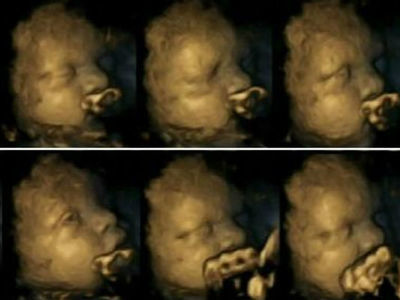

Imagens Chocantes Mostram Diferenca Entre Fetos De Maes Fumantes E Nao Fumantes